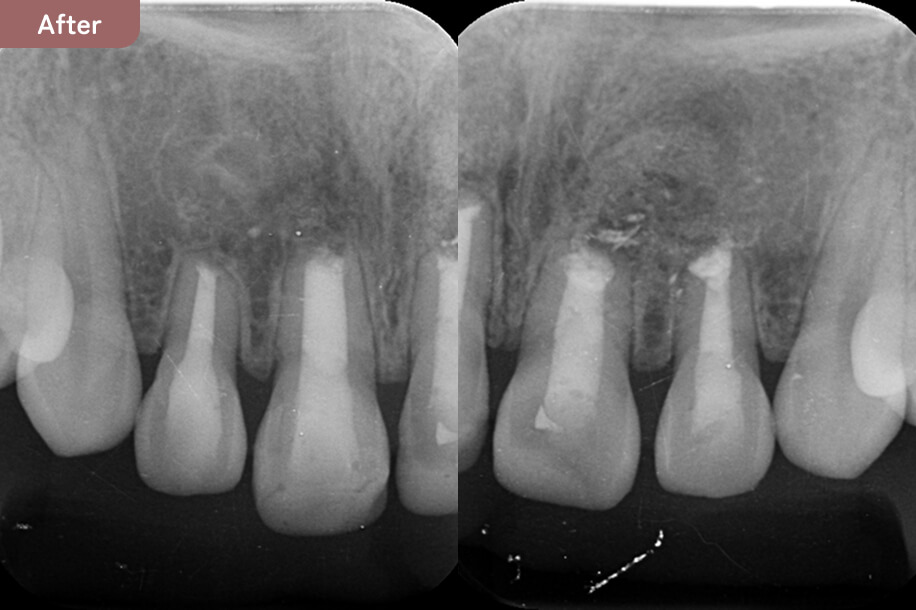

大学病院でも治らず、根の先に大きな骨吸収があり腫れていた。

自費根管治療と歯根端切除術を行い、骨の再生が起こり、症状がなくなった。